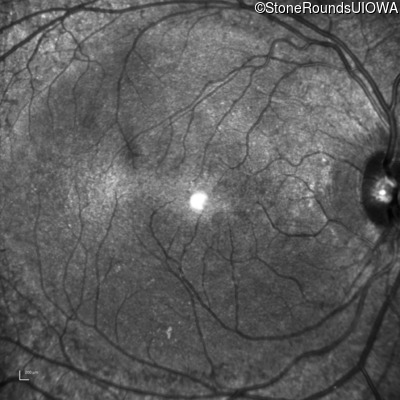

Infrared Fundus Photograph - Right - 20/25

Exemplar